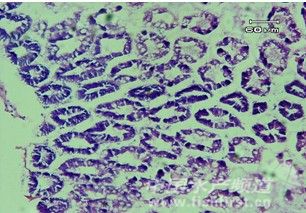

圖1示患病對(duì)蝦肝胰臟的腫大和萎縮 1.2對(duì)蝦肝胰臟和中腸的組織學(xué)觀察 通過(guò)顯微鏡觀察,發(fā)現(xiàn)正常對(duì)蝦和患病對(duì)蝦肝胰臟和中腸的組織形態(tài)有很大的差異。正常對(duì)蝦的肝胰臟為復(fù)管狀腺,由多級(jí)分支的肝小管組成,肝小管管壁由單層細(xì)胞構(gòu)成,管腔呈五角或四角星形,腺細(xì)胞正常(圖2);中腸管壁組織厚度均勻、致密,腸腔中充滿內(nèi)含物(圖4)。患病對(duì)蝦肝胰臟的腺細(xì)胞間隙變大,腺細(xì)胞核變小,腺細(xì)胞有不同程度的自溶現(xiàn)象,肝小管變形(圖3);中腸腸壁變薄,腸粘膜脫落并散落于腸腔內(nèi),腸腔中沒有內(nèi)含物(圖5)。

圖2正常南美白對(duì)蝦的肝小管橫切面

圖3患病南美白對(duì)蝦的肝小管橫切面